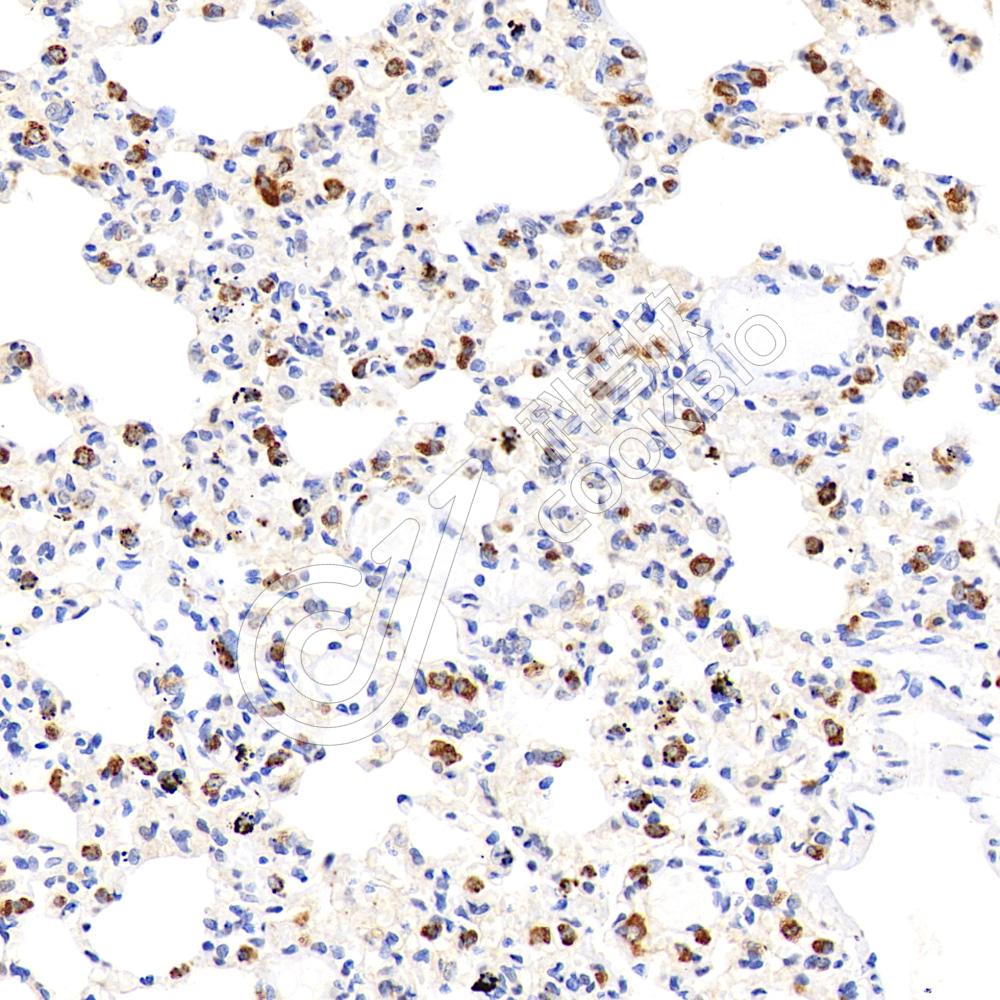

IHC检测Cytochrome P450 Reductase蛋白(货号 K1339999).

样品: 大鼠肺, 4%多聚甲醛 (货号KSG1101) 固定12-24小时.

抗原修复: 柠檬酸抗原修复液(干粉, pH 6.0) (KSG1201), 98℃, 20分钟.

—抗: 1: 2300稀释, 4℃ 孵育过夜.

二抗: S-vision免疫组化多聚二抗(山羊抗兔),即用型 (货号KB3906), 室温孵育20分钟.